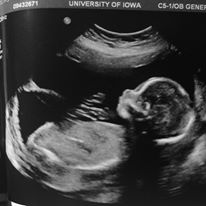

We showed up and had the first ultrasound. Everything looked fine.